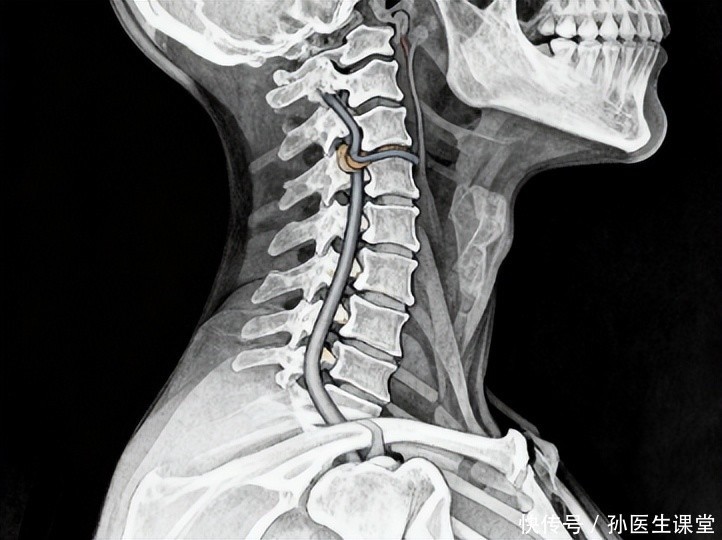

在就医前,可先停下大幅度转头与仰头动作,平躺或侧卧,让颈部保持中立位;松开衣领,安静休息,切勿自行大力“扳脖子”;把诱因、持续时间、伴随不适以及既往基础疾病记录好,带去给医生参考。就诊可选择神经内科(或急诊),医生或会根据需要评估血压、颈椎影像及脑后循环血流状况。